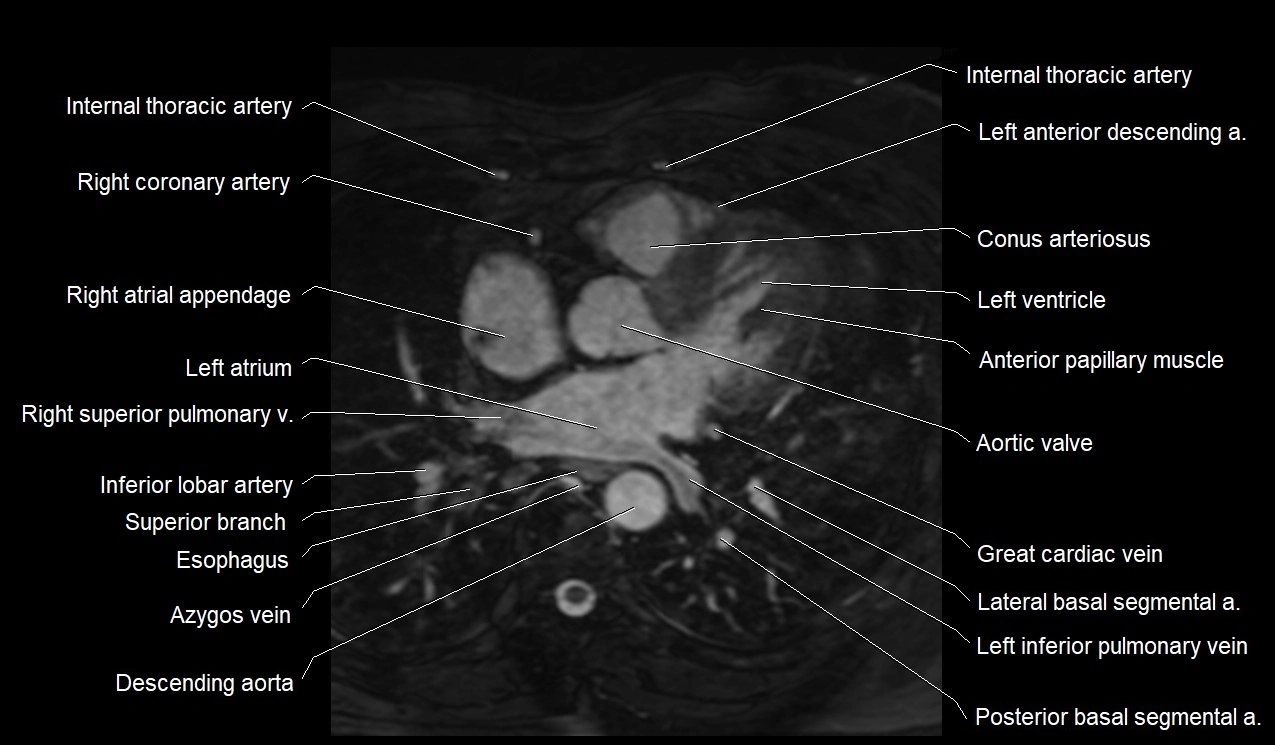

MRI image